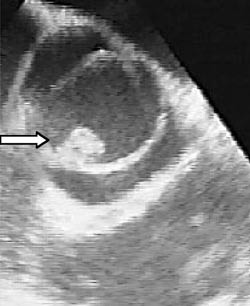

Pasient 3. En tidligere frisk 38 år gammel mann våknet ca. en uke før innleggelsen med sterke ryggsmerter. Han ble behandlet for en antatt lumbago med smertestillende midler, bl.a. morfin. Til tross for dette progredierte smertene og han ble innlagt i sykehus. Ved innkomsten var han fullstendig immobilisert pga. smerter. Temperaturen var 37,7 ºC, CRP 246 mg/l, SR 79 mm og Hb 13,4 g/100 ml. Lasègues test var positiv ved 35 ºC. Alfahemolytiske streptokokker (Streptococcus oralis) ble påvist i blodkulturen. CT av LS-columna viste et stort venstresidig prolaps i nivå L5/S uten tegn til spondylodiskitt. Imidlertid viste MR en spondylodiskitt i samme nivå (fig 1). Transøsofageal ekkokardiografi viste en bikuspid aorta med store vegetasjoner (fig 2). Det ble startet behandling med gentamicin og penicillin. Seks dager etter påbegynt behandling måtte han overflyttes til regionsykehus fordi han utviklet symptomgivende aortainsuffisiens. Transtorakal ekkokardiografi viste en fistel til høyre ventrikkel like under trikuspidalklaffen, samt en stor aortainsuffisiens. Han fikk innsatt en mekanisk aortaklaffprotese, men utviklet postoperativ pneumoni og nyresvikt og måtte respiratorbehandles. Dyrking av klaffen gav ingen oppvekst. Han utviklet totalt AV-blokk og fikk implantert permanent pacemaker. Han er nå tilbake i arbeid.

Ekkokardiografisk undersøkelse er meget viktig for å stille diagnosen endokarditt. Transtorakal tilgang er rask og enkel, men angis å ha en sensitivitet på under 50 %, mens transøsofageal tilgang gir en sensitivitet på over 90 %. Begge undersøkelser har en spesifisitet på over 95 % (15).